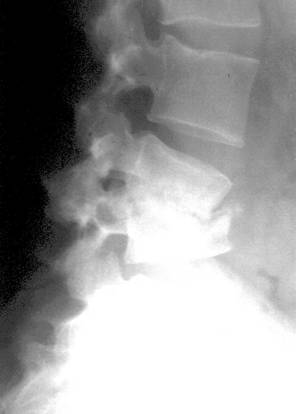

- nearticulare - cu forme si dimensiuni diferite, numite: protuberante, procese, tuberozitati, spine, creste;

Gauri si canale: sunt de doua feluri: de trecere si de nutritie, numite diferit foramen, hiatus, fosa, incizura, duct.

Nucleii secundari de osificare – sunt situati la extremitatile osului si apar la varste diferite. Din acesti nuclei rezulta epifizele si apofizele.

Cartilajele de crestere – sau cartilajele epifizo-diafizare apar radiologic sub forma unor benzi radiotransparente ce separa complet epifiza de diafiza; au contururi usor ondulate si sunt simetrice.